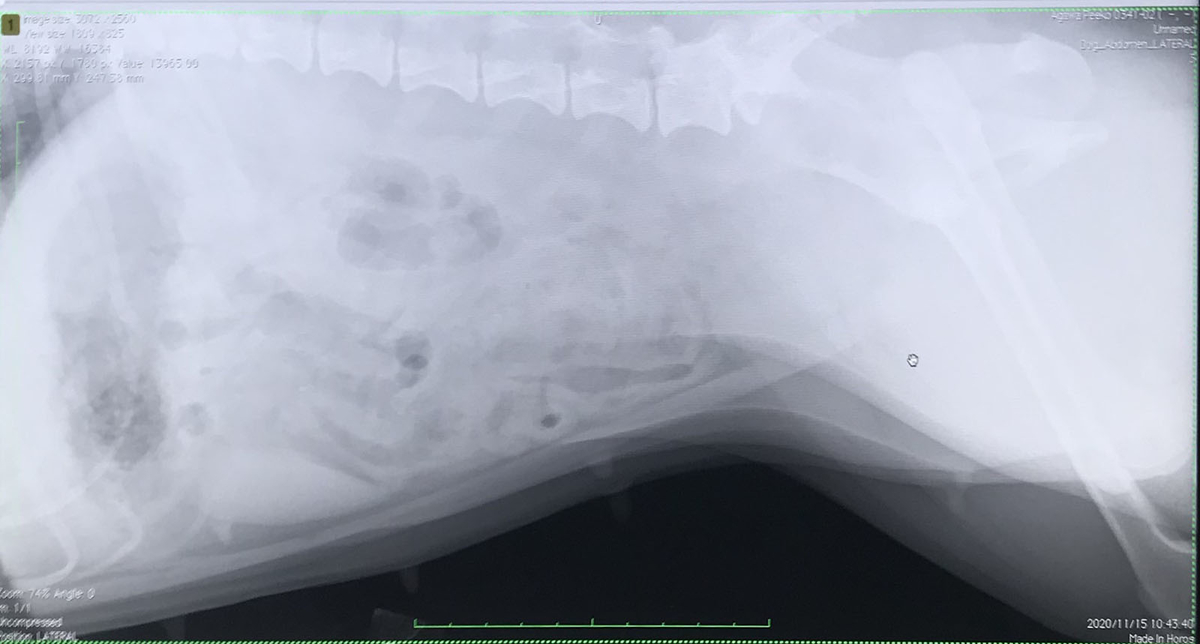

その後は繊維の多いサツマイモを食べさせながら、毎日のウンチ💩を確認して4日後に再度レントゲン撮影。幸い腸内は奇麗になっていました。

ピィ子、綺麗に出た〜〜!!

注目のレントゲン再検査。芝生の公園で遊んでから動物病院へ。

結果は綺麗に出ていました。よって水曜日が避妊手術です。

今回分かったことーー

芝生では遊んで大丈夫。

そして、お芋ありがとう!#犬を飼うということ#ピィ子#ブルテリア#出すもの出した#スッキリ pic.twitter.com/yZb8OdeY7R